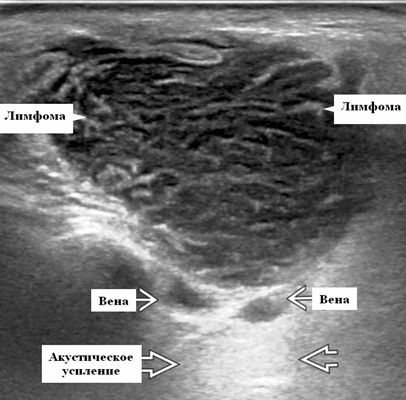

Серошкальное УЗИ. Узловая НХЛ. Одиночные или множественные увеличенные яйцевидные внутрипаротидные лимфатические узлы. Гомогенно гипоэхогенный по отношению к паренхиме околоушной железы. Сетчатый эхосигнал. Заднее акустическое усиление. Первичная паренхиматозная НХЛ. Рассеянный, неоднородный эхосигнал; нечеткие, гипоэхогенные, похожие на опухоль участки. В пунктате внутрикистозная или паренхиматозная кальцификация из-за конечной стадии воспалительного изменения. Небольшие кистозные области образуются из-за сдавления терминальных протоков лимфоидной гипертрофией. Множественные небольшие гипоэхогенные участки (представляют собой лимфоидные агрегаты), разбросанные на фоне ткани слюнной железы. Изменения могут имитировать хронический сиалоаденит и диагноз часто ставится при биопсии. На УЗИ необходимо искать аналогичное поражение других слюнных и слезных желез, фон синдром Шегрена, BLEL. Может иметь или не иметь перипаротидную и шейную лимфаденопатию

- Используя современные датчики высокого разрешения, несмотря на их солидную природу, лимфоузлы НХЛ имеют тенденцию к заднему усилению

Ультрасонографические данные. Узлы НХЛ обычно круглые с четкими границами. Отложение опухоли в узлах создает больший акустический импеданс между узлом и прилегающими мягкими тканями, что приводит к резкой границе. Нерезкая граница указывает на экстракапсулярное распространение, подразумевая агрессивное заболевание неходжкинской лимфомы. Солидный узел и отсутствие нормальных эхогенных ворот встречается у 72-73% пациентов.

Обычно на УЗИ это гипоэхогенный лимфоузел по сравнению с соседними мышцами и ранее описывалось как псевдокистозные узлы с задним усилением. При использовании более старых преобразователей внутренние эхосигналы в узлах были очень низкими, почти анэхогенными, напоминающими кисту. Используя современные датчики высокого разрешения, несмотря на их солидную природу, мы видим, что узлы НХЛ имеют тенденцию к заднему усилению. Равномерная клеточная инфильтрация внутри узлов создает меньше границ между структурами и облегчает прохождение ультразвука. Это, в сочетании с низкой внутренней эхогенностью, приводит к так называемому псевдокистозу. Лимфоузлы неходжкинской лимфомы показывают интранодальный ретикулярный или микронодулярный рисунок с использованием более новых преобразователей высокого разрешения